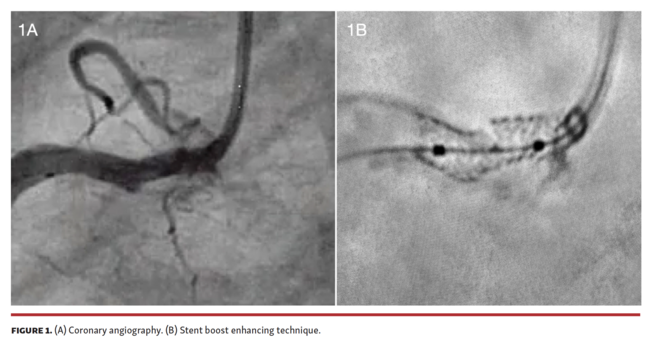

Three months later, the patient was readmitted for NSTEMI. CAG revealed a complete separation of 2 stent segments, indicating a stent fracture (Figure 1 and Video 1). Intracoronary optical coherence tomography (OCT) showed intraluminal non-endothelized strut protrusion at the fracture frame, and ostial underexpansion due to severe concentric calcification (Figure 2 and Video 2). High-pressure dilation was performed (3.0 x 15 mm non-compliant balloon) followed by coronary lithoplasty with a 4.0 mm Shockwave balloon (Shockwave Medical) in the ostial underexpansion. Finally, a 4.0 x 23 mm everolimus-eluting stent was deployed, covering the fracture and stent edges, achieving a good result by angiography and OCT (Videos 3 and 4).

The Synergy Megatron stent confers enhanced axial and radial forces, which makes it an ideal choice for ostial and calcified lesions. However, in this case, the stent fractured. The mechanical stress due to severe calcification at the ostium, followed by a swinging segment, probably caused hinge effect and led to a stent fracture (Figure 2C). The fluoroscopy and stent-enhancing techniques suggest and could confirm the diagnosis, but intracoronary imaging is mandatory for anatomy characterization in order to decide treatment and optimize the result.